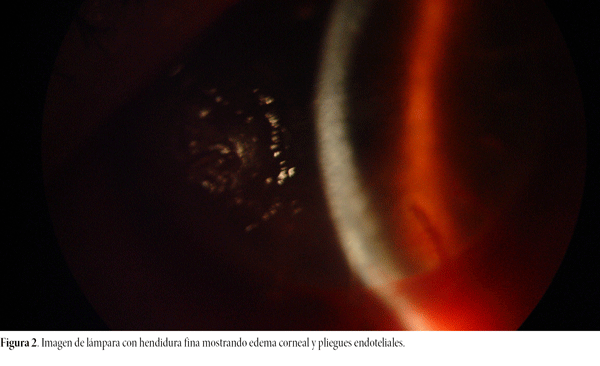

Se recibe para su evaluación, estudio y tratamiento. Vemos dos pequeños infiltrados en puntos ya retirados, múltiples neovasos sobre el injerto, edema corneal más intenso en córnea central e inferonasal, pliegues endoteliales y precipitados queráticos finos (figs. 1 y 2), AV cuenta dedos, inyección conjuntival, células en cámara anterior, queratitis punctata inferior y tinción inespecífica con fluoresceína sobre el injerto (fig. 3). Presión ocular e iris, normales. Se realiza toma de muestra corneal para examen directo, cultivo para bacterias, hongos y amebas. PCR panfúngica, PCR para Acanthamoeba y PCR para virus HSV-1 y HSV-2.

Figura 2. Imagen de lámpara con hendidura fina mostrando edema corneal y pliegues endoteliales.